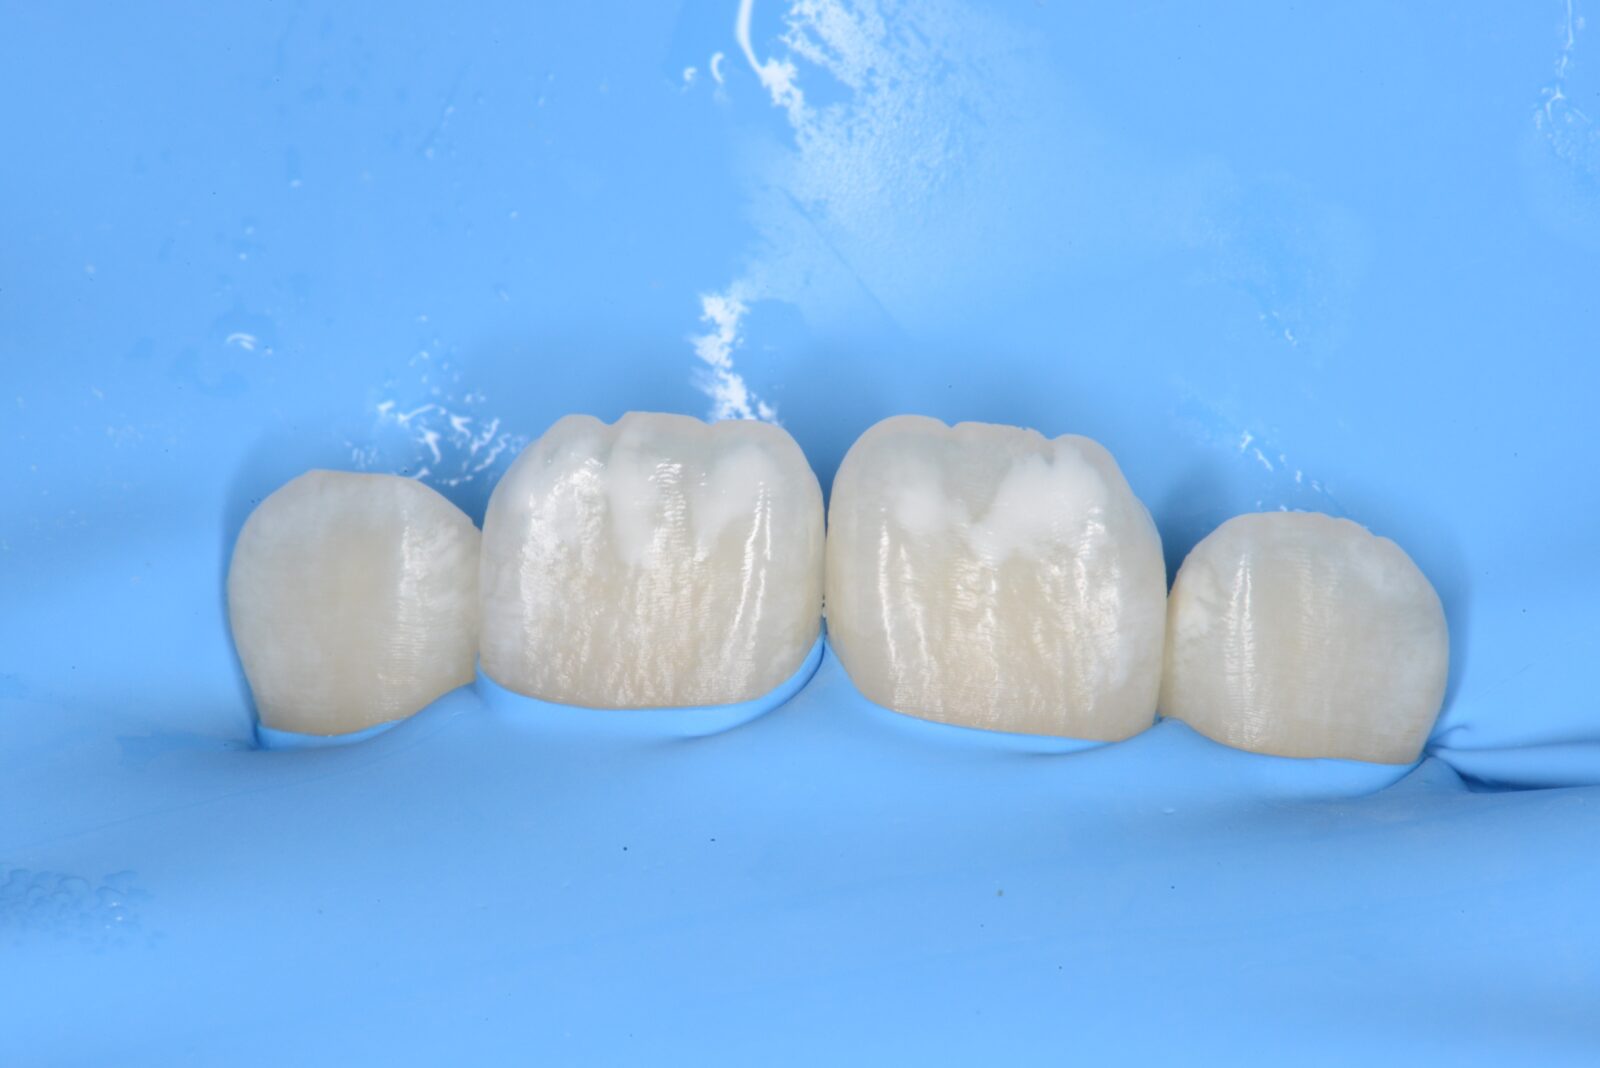

左上6,7ダイレクトボンディング

左上6➡他院で治療したセラミックスの接着不良からの二次感染。 左上7➡コンポジットレジンの接着不良からの二次感染。   ともに、旧充填物と感染歯質を除去後、歯面処理と接着操作を行う。 その後、ダイレクトボンディングにて、充填処置を行い、ティント(ブラウンとホワイト)…